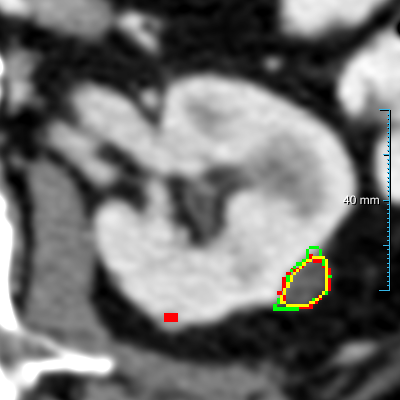

Case 1: 0.346 Dice score

Case 2: 0.266 Dice score

Case 3: 0.777 Dice score

(a) Input slice

Refer to caption

(b) Pred. of experiment 1

(c) Contours

Figure 7: Comparison of three cases on the test set B30 between experiment 1  , the reference standard, and the second observer. (a) shows the original slice. (b) shows the heatmaps (predictions prior to post-processing, using a color table mapping [0,1] from transparent to green to red) of experiment 1  . (c) shows the final predictions (red contours) of experiment 1  , the reference standard (green contours), and the second human observer (yellow contours). The window center and window width used for all slices were 60 HU and 360 HU.

Segmenting kidney abnormalities is challenging due to the similarity between tumors in the collecting system and kidney cysts. For instance, Figure 7 shows three cases from dataset B30 where our method returned some false positives due to the similarity with tumors in the collecting system. Each case shows the kidney abnormality predictions of experiment 1   prior to post-processing in the second row as heatmaps. While the third row shows the post-processed segmentation, reference standard, and second observer as red, green, and yellow contours, respectively. In all three cases, a false positive by our method is present, indicated by an isolated red contour. In case 1, the false positives are abnormalities in the collecting system, which have a similar image intensity as the cysts, similarly, the second observer also segmented one of these abnormalities in the middle region. In case 2, the false positive appears as a small cyst-like region, while in case 3, it resembles an irregular region in the kidney. Figure 9 shows a comparison of the final prediction in annotation format 1 of experiment 1  , the reference standard, and the second observer represented as red, green, and yellow contours, respectively. This figure shows the best and median cases of datasets B20 and B30 and the Dice score of each case computed between experiment 1   and the reference standard.